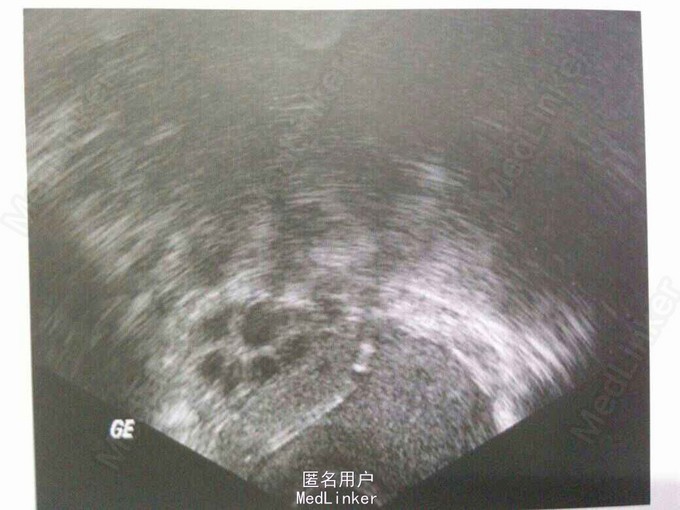

患者,女,40岁 主诉:节育器置入术后10年 现病史:10年前上环,现复查。上环后月经正常,无明显不适,2年前复查B超示位置正常

未行妇检 辅助检查:B超示子宫正常大小,节育器呈条状,前端突入子宫前壁10mm